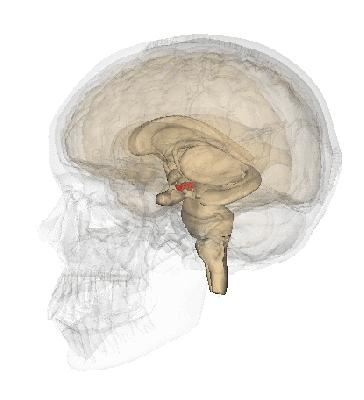

脑部

脑干